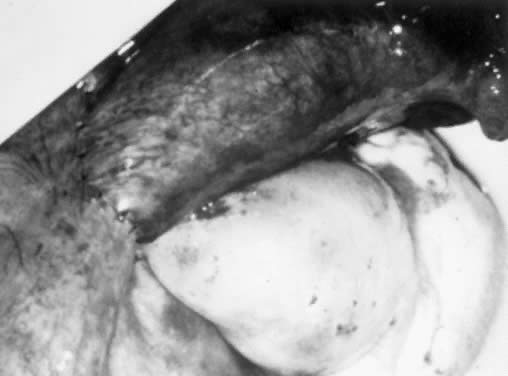

The surgical treatment of cornual occlusion by uterotubal implantation has been replaced by cornual-isthmic reanastomosis because of its superior postreversal pregnancy rates of 46% to 69%.23,24,25,26,27,28 The technique involves preparation of the isthmic portion of the tube similar to that with isthmic-isthmic reanastomosis, with some modification of the cornual side. With a small blade, such as a no. 15 Bard-Parker scalpel, the cornual region is shaved serially. One-millimeter slices are removed until patency is shown (Figs. 7 and 8). Bleeding areas are controlled, preferably by microbipolar cautery, to minimize tissue injury. After the stay sutures of 6-0 Vicryl are placed to align the lumens, a two-layer reanastomosis is performed (Fig. 9). A splint is used, but it is removed at the end of the procedure. A cornual-ampullary reanastomosis is more difficult than a cornual-isthmic procedure because of the large discrepancy in lumen diameter of the ampulla. The best recommendation is to make the ampullary diameter as small as possible, as recommended for the isthmic-ampullary reanastomosis.

Fig. 7. The cornual region is shaved until patency is shown.

Fig. 8. Cornual resection.(Courtesy of Marvin Yussman, MD.)